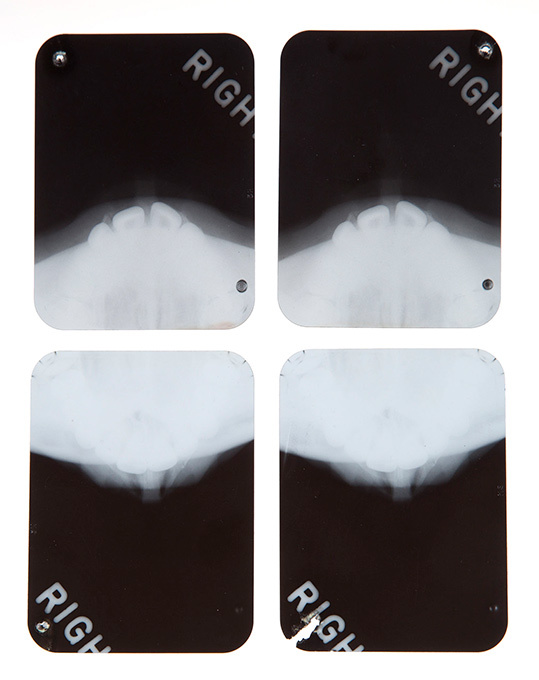

Организаторы Julien's Auctions хотят раскрыть одну из самых главных тайн Голливуда. Медицинский архив содержит рентгеновские снимки и записи врачей, у которых наблюдалась голливудская звезда.

В пресс-релизе события говорится об операциях по коррекции формы носа и подбородка Мэрилин.